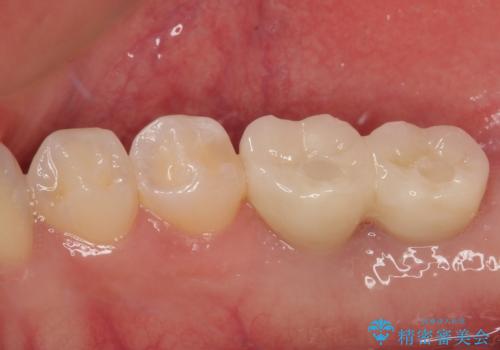

その後、挺出していた右上第一大臼歯と第二大臼歯に装着されていた銀歯についても、審美性と適合性の向上を目的に、オールセラミッククラウンにやり替えました。

これにより、より自然で美しい見た目と、高い精度の咬合が得られています。